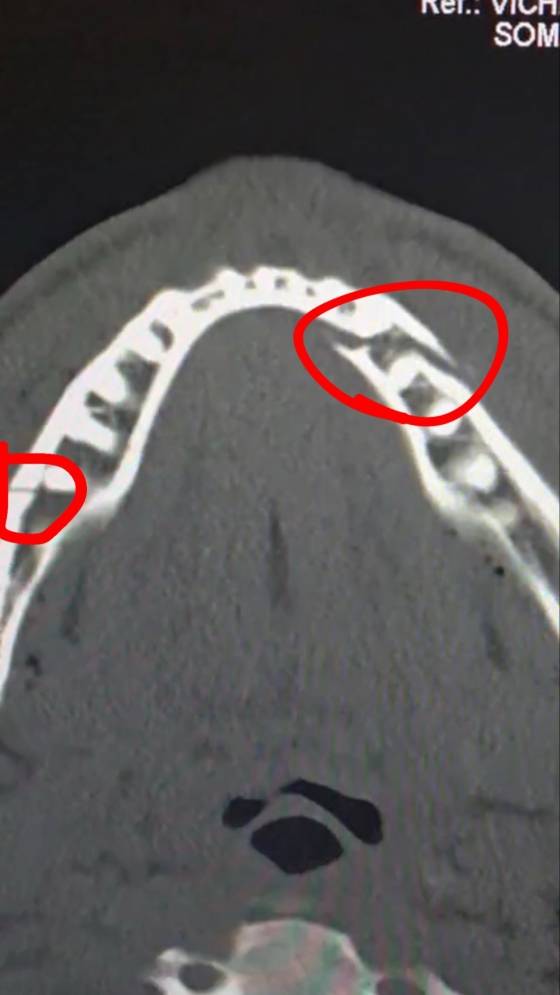

부상의 정도는 상상을 초월했다. 폴은 부러진 턱을 고정하기 위해 티타늄 플레이트 두 개를 삽입하고 일부 치아까지 제거하는 대수술을 두 차례나 견뎌냈다. 폴은 지난주만 하더라도 "다시 스파링을 시작하기까지 최소 6개월은 걸릴 것"이라며 당분간 공백기가 이어질 것을 시사했다.